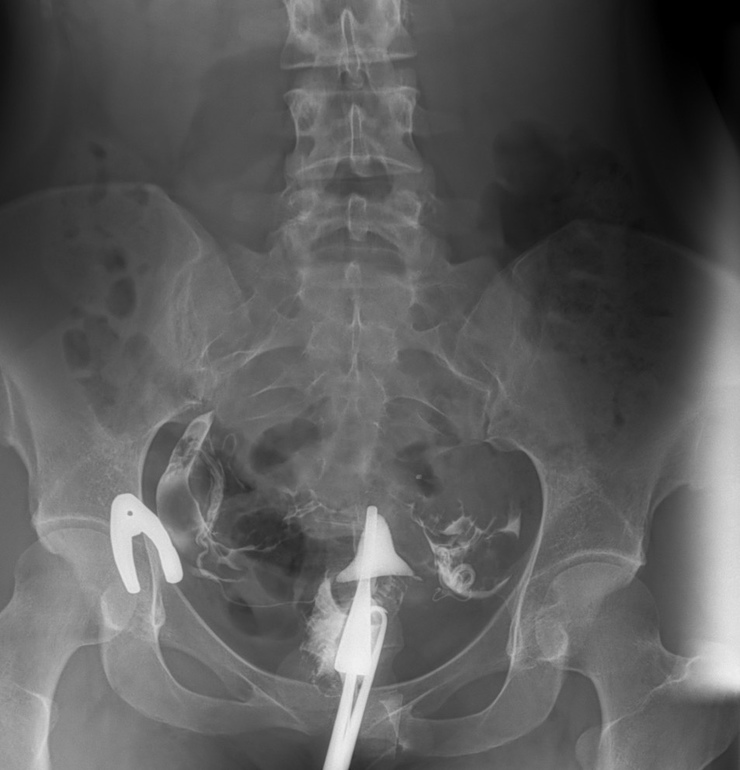

На мой взгляд обе трубы проходимы, потому что контраст вышел и справа, и слева. Видите эти белые облачка-кляксы на втором и третьем снимке? Это оно! Можете погуглить снимки других женщин и поймете, что я имею ввиду. Также есть форум рентгенологов. Можете там посмотреть на чужие снимки и свой показать. Они бесплатно прокомментируют.